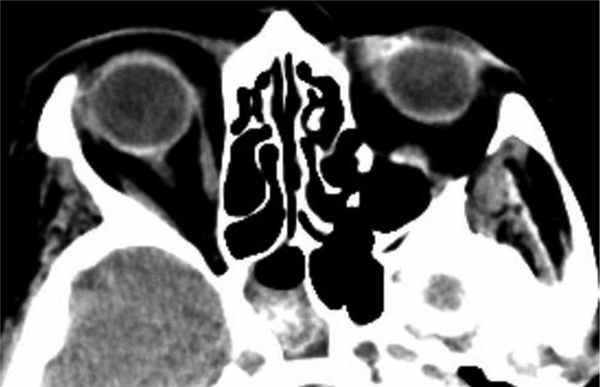

В 22 (75,9%) случаях была поражена клиновидная пазуха, у 6 (20,7%) пациентов — клетки решетчатого лабиринта, в том числе у 1 больного — большой решетчатый пузырек (рис. 2). Рис. 2. Больной К., 58 лет. КТ околоносовых пазух (а) с реконструкцией в коронарной проекции (б). Грибковое тело в проекции большого решетчатого пузырька слева (указано стрелками). The fungal body in the left-hand projection of the ethmoidal bulla of nasal cavity (indicated by the arrows). В 1 (3,4%) случае отмечалось поражение лобной пазухи (рис. 3, 4). Рис. 4. Локализация изменений у пациентов с экстрамаксиллярным синуситом. Fig. 4. Localization in the patients presenting with extramaxillay sinusitis. Рис. 3. Больная А., 48 лет. КТ лобных пазух (а) с реконструкцией в коронарной (б) и сагиттальной (в) проекциях. Грибковое тело в лобной пазухе справа (указано черной и белыми стрелками). The fungal body in the right-hand frontal sinus (indicated by the black and white arrows).

Во всех изученных случаях в околоносовых пазухах определялись высокоплотные включения. Одна группа включений в виде четко очерченных единичных и довольно крупных очагов уплотнения, которые определялись в костном окне просмотра изображений была выявлена у 11 (37,9%) человек, другая — в виде множества мелких нечетко очерченных очагов, которые не определялись или определялись плохо в костном окне просмотра изображений, — у 18 (62,1%) пациентов (рис. 6). Рис. 6. Больная М., 75 лет. КТ в аксиальной проекции. Правосторонний грибковый сфеноидит (указано черной стрелкой). В мягкотканном окне определяются мелкие множественные гиперденсивные включения (а), которые в костном окне не определяются (б). Left-had mycotic sphenoiditis (indicated by the black arrow). Multiple hyperdense inclusions can be seen in the soft tissue window (a) undetectable in the bone window (b).